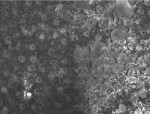

Figure 4a, Figure 4b and Figure 4c provides SEMs of cross sections of the dentin, which was treated with each of the calcium- and phosphate-containing fluoride toothpastes—E, AHECS, and AHEC. Each figure shows mineral covering the dentin surface and blocking most of the tubules. The layer produced by AHECS looked very similar to that resulting from treatment of dentin with the professional desensitizer. Furthermore, it appeared to be strongly bonded to the dentin.

The calcium- and phosphate-delivering toothpastes apparently operate by a similar mechanism to the professional desensitizer, producing ACP that transforms into HAP on the surface of the dentin, sealing tubules and reducing dentin permeability. The morphology of the surface mineral produced by E and AHEC is not clearly seen in these SEMs. However, the mineral created by AHECS appeared strikingly similar to that made by Q. In both cases, the mineral appeared strongly bonded to the dentin surface.